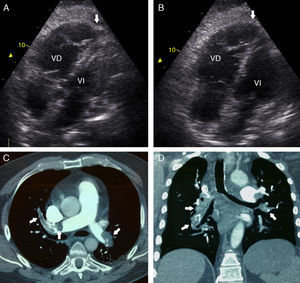

Paciente varón de 53 años que comienza con cuadro de disnea, fiebre y dolor torácico pleurítico, de inicio súbito. A su llegada a urgencias presentaba hipotensión, taquicardia y saturación arterial del 80% respirando aire ambiente. El electrocardiograma mostró taquicardia sinusal con patrón S1Q3T3 con ondas T negativas de V1-V6. Con una alta sospecha de tromboembolismo pulmonar (TEP), se practicó un ecocardiograma portátil (EP) urgente que mostró dilatación y disfunción del ventrículo derecho (VD), con preservación de la contractilidad del ápex (signo de McConnell [SMC]) (fig. 1A-B) y datos indirectos de hipertensión pulmonar severa. Ante la inestabilidad hemodinámica se optó por realizar fibrinólisis con alteplasa (rtPA), con buena respuesta clínica. Tras su estabilización, se realizó angiotomografía de tórax que confirmó la presencia de un TEP bilateral extenso con signos de recanalización incipientes (fig. 1C-D, flechas). Un eco-doppler confirmó la presencia de trombosis venosa profunda femoropoplítea derecha. Fue dado de alta sin complicaciones

A) Ecocardiografía. La imagen de 4 cámaras en sístole muestra acinesia de la pared libre del VD con hipercinesia del ápex (flecha). B) Ecocardiografía. Imagen de 4 cámaras en diástole, dilatación del VD, ápex de VD (flecha). C) Angiotomografía de tórax con contraste, plano axial. Trombos intraluminales en ambas ramas pulmonares con recanalización parcial (flechas). D) Angiotomografía de tórax con contraste, plano coronal. Trombos intraluminales en ambas ramas pulmonares (flechas). VD: ventrículo derecho; VI: ventrículo izquierdo.